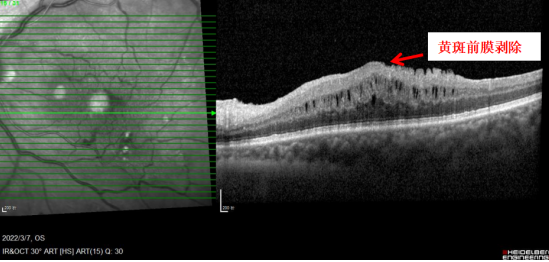

问诊中,老杜说自己左眼看东西模糊,而且会发生变形。郑宏华主任随即拿出一张方格表(阿姆斯勒表)让老杜看,并作答,结果发现老杜左眼看到的直线都是扭曲的。为了进一步明确病情,郑宏华主任为老杜完善了各项专科检查,“OCT检查显示患者黄斑水肿,黄斑前膜已经进展到晚期,严重牵拉视网膜导致视物变形,需要尽快进行手术剥膜!”

手术前的OCT检查↑

手术后OCT检查,黄斑前膜剥除,黄斑形态缓慢恢复↑